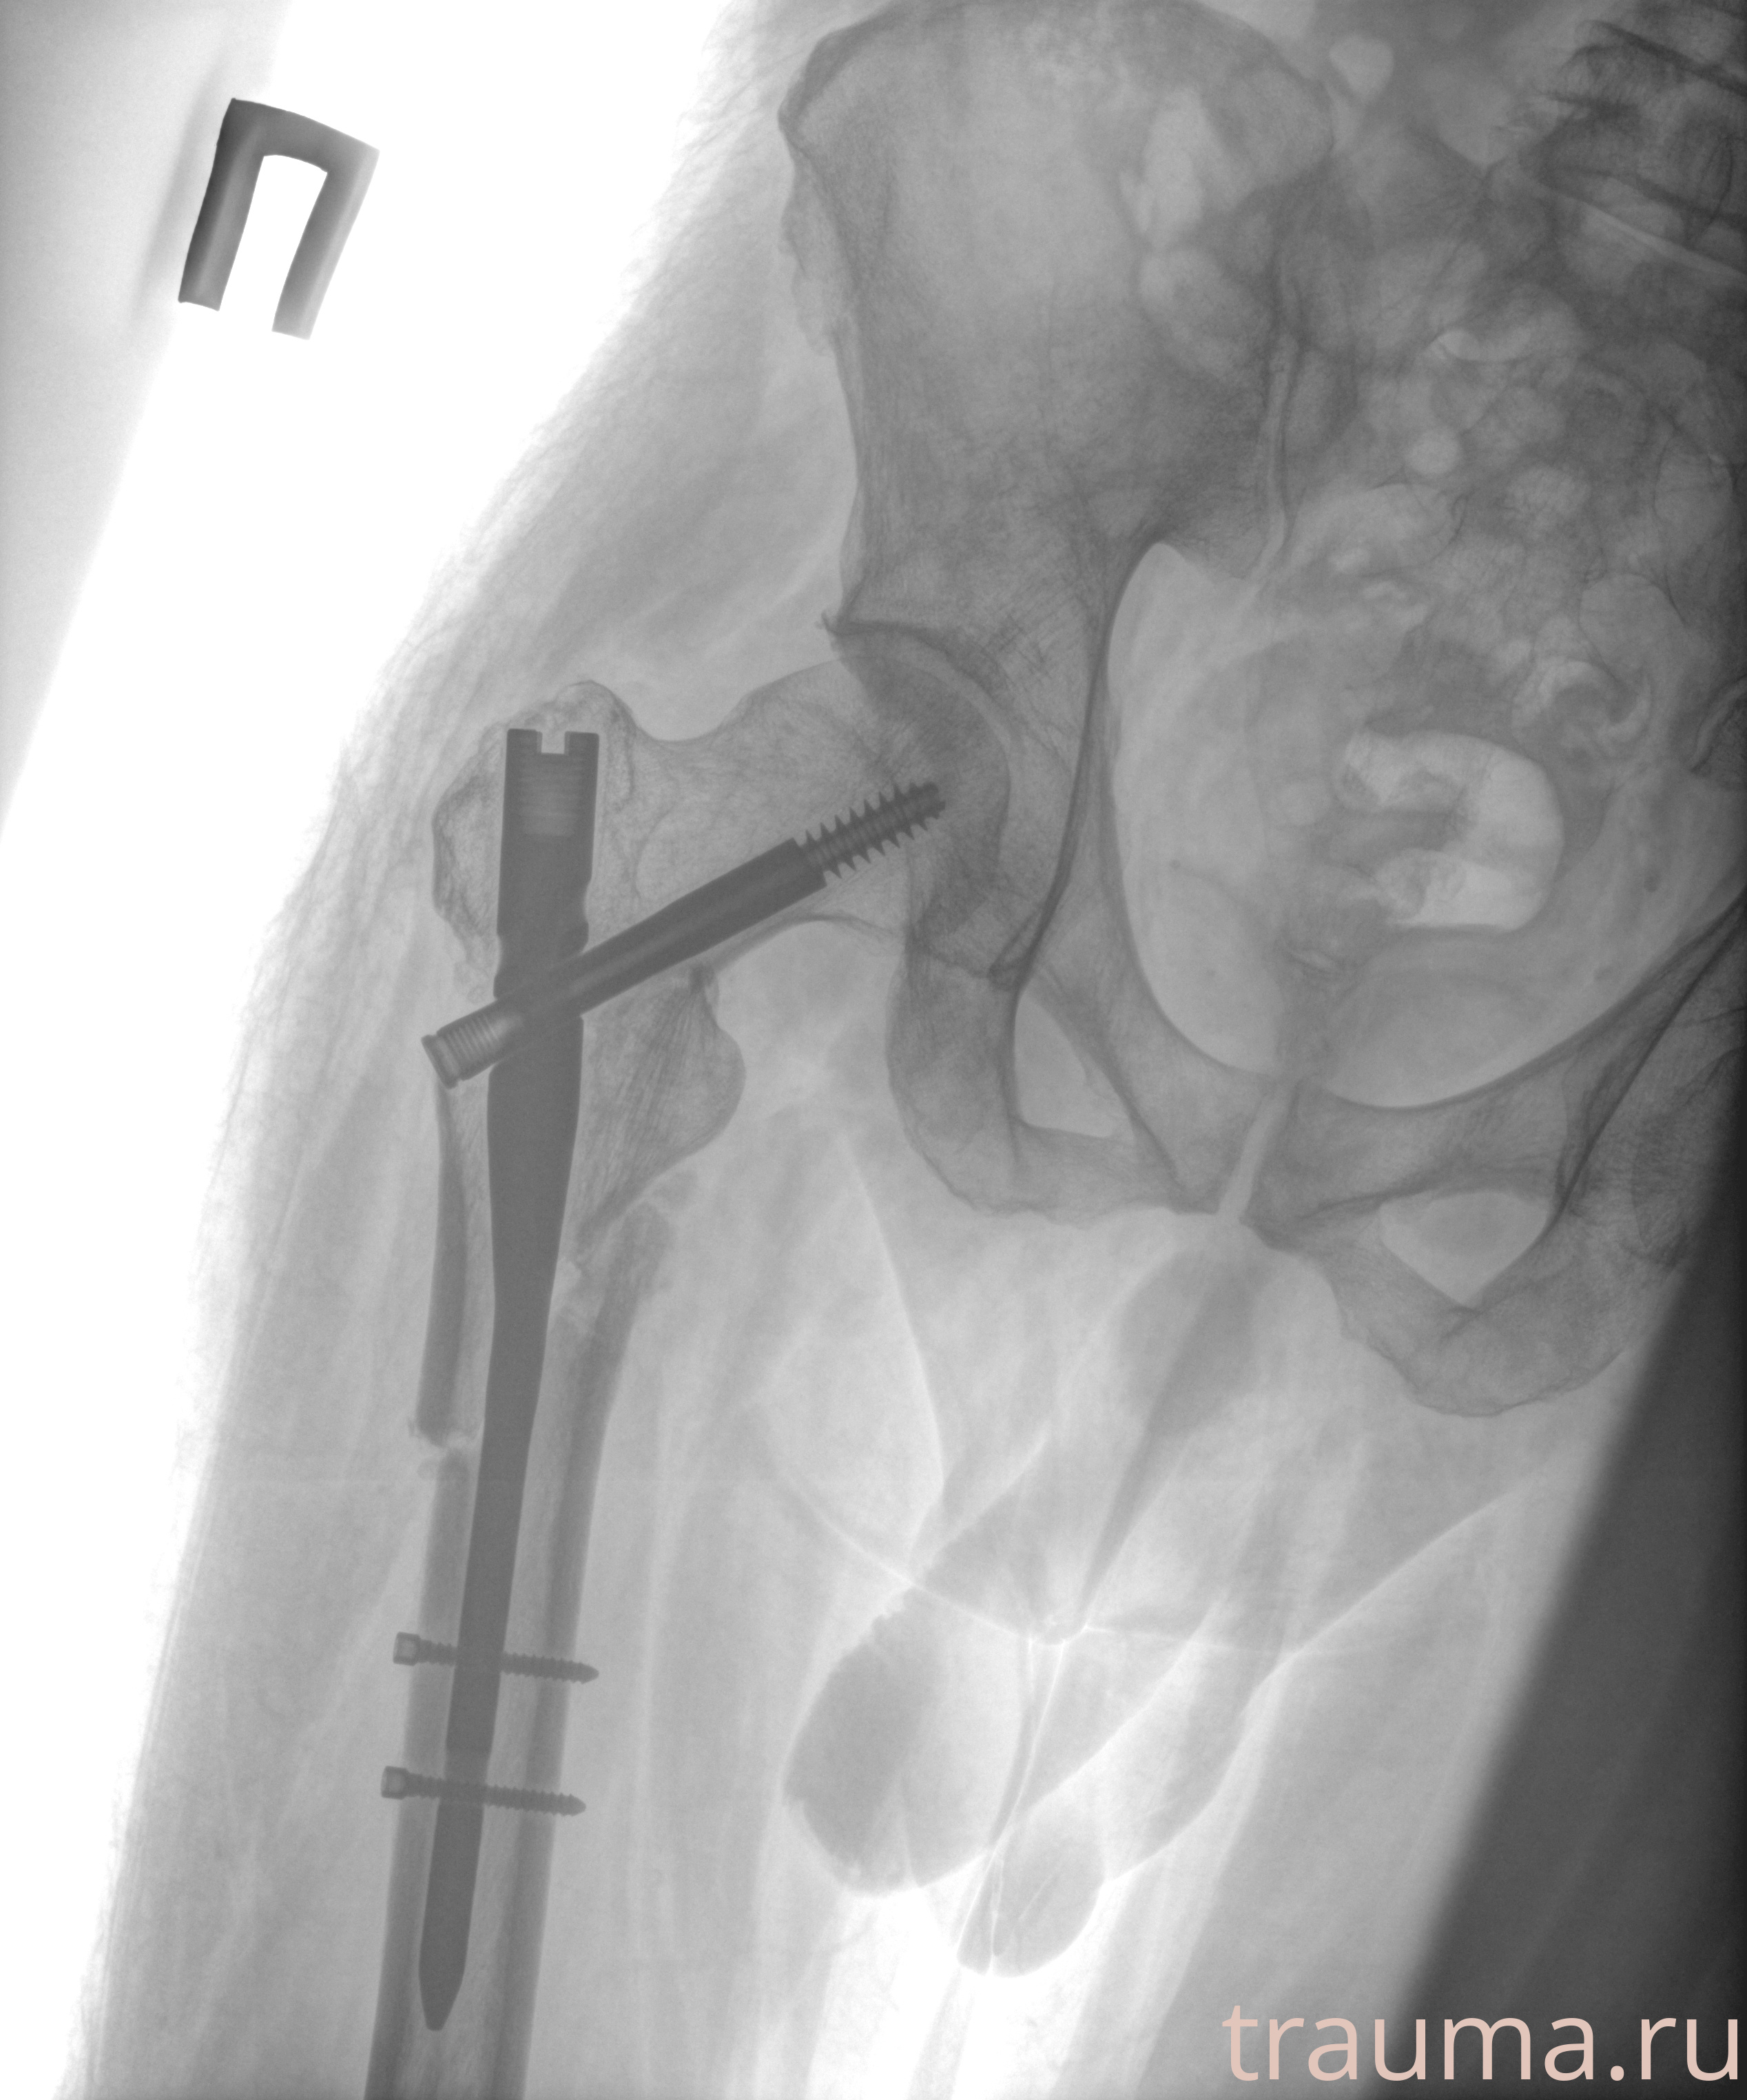

Рентген на дому: по вашему адресу приезжает врач-рентгенолог, травматолог-ортопед с мобильным рентгеновским аппаратом, проводит диагностику травмы или заболевания, делает необходимые рентгенограммы, дает рекомендации по дальнейшему лечению. Получить качественные снимки в домашних условиях возможно благодаря уникальной методике, разработанной МосРентген Центром для института  Склифосовского